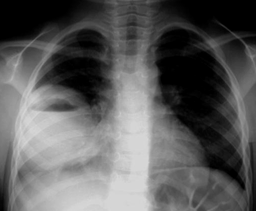

X线检查可见局部浓密炎症阴影,中有气液平面。

影像:气液平面